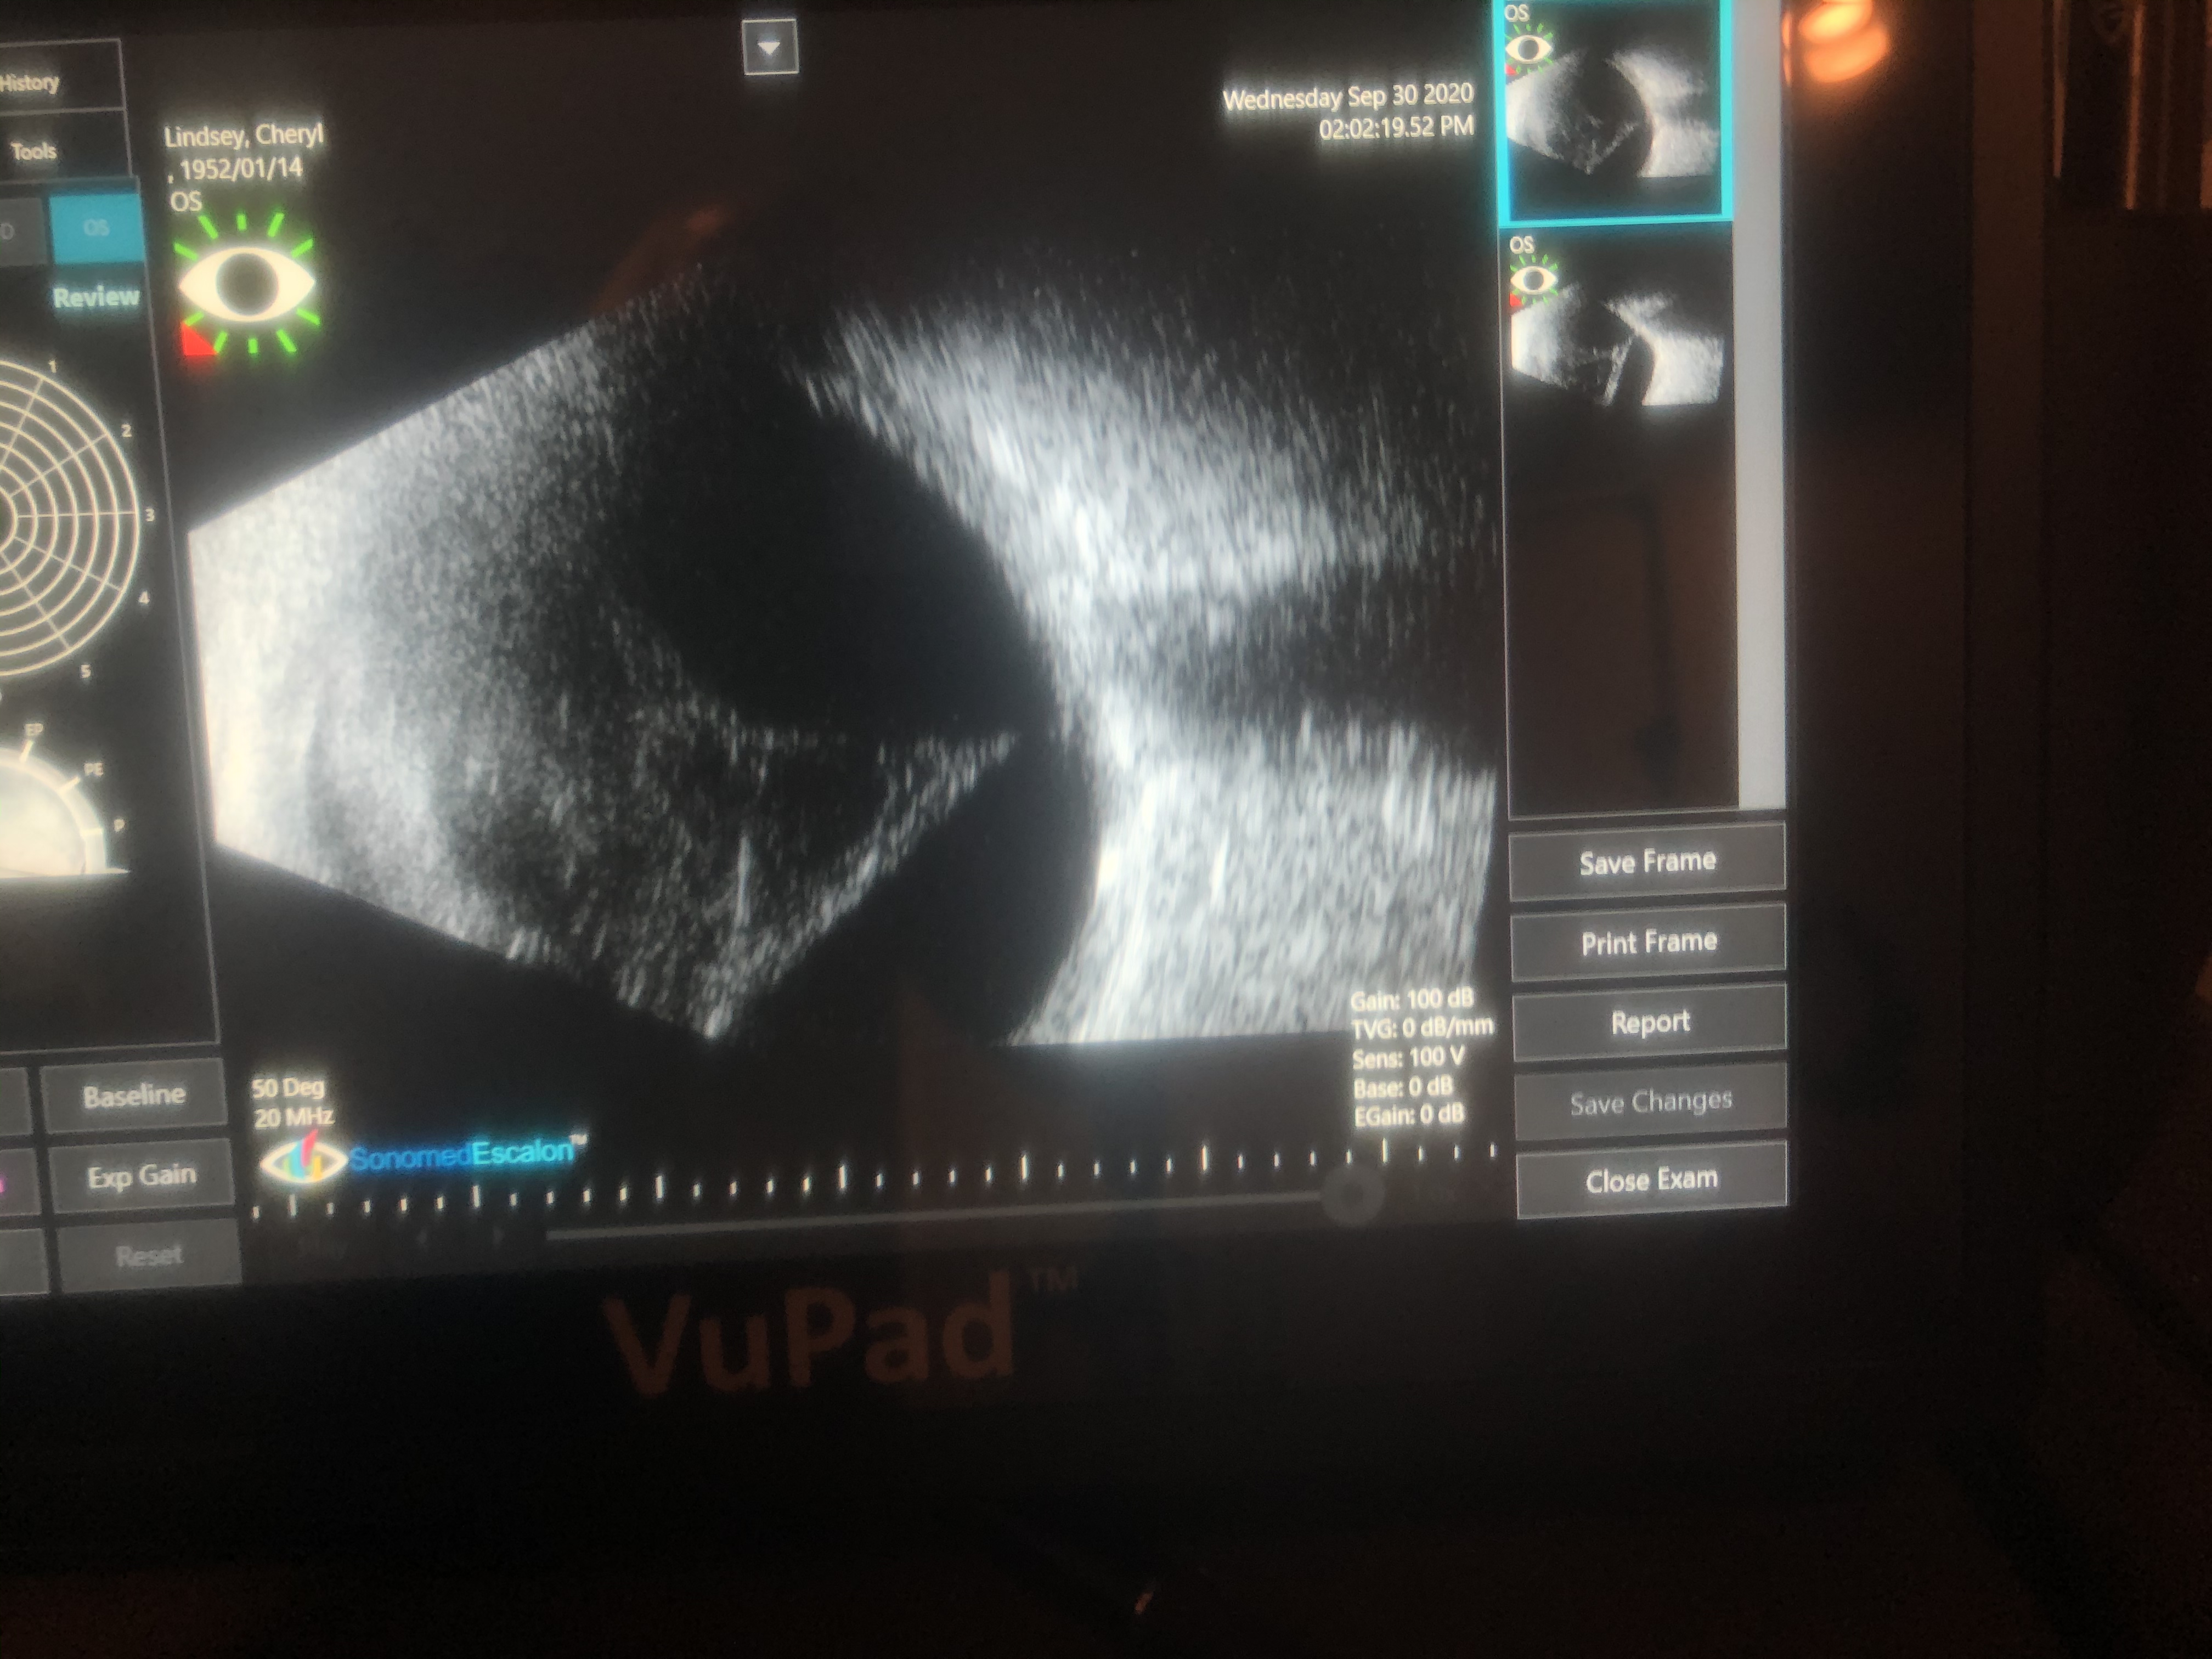

In the photo above the left side is the front of my eye.  The right side is the optical nerve and blood vessels.  The triangular spiderweb in the middle is what they’re going to remove tomorrow.  Right now I see the world through a cloud.  They’re also repairing a spot on the cornea where the new lens was installed in August so my eye opening to the world will be a regular circle.  The spiderweb has distorted it somewhat.  I’ve been dilating my eye with drops twice a day for 2 months to keep it from closing completely off.